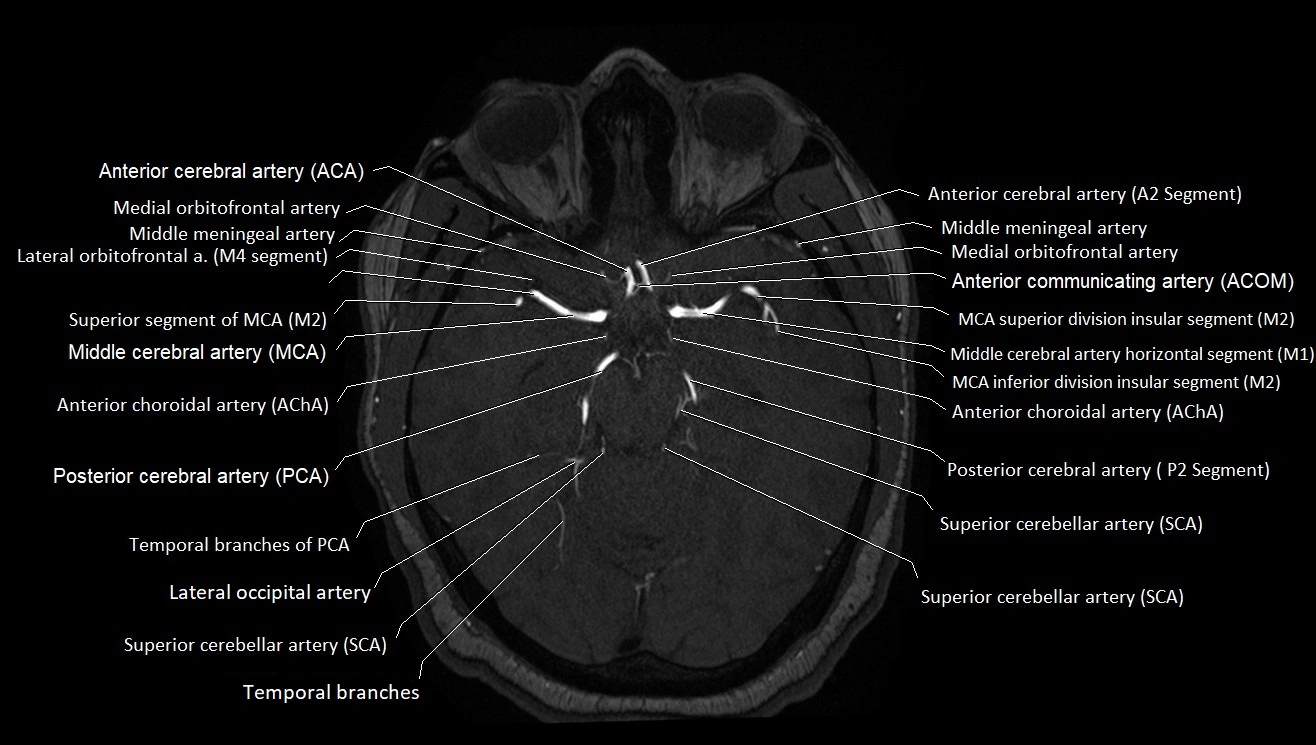

MRI images

image